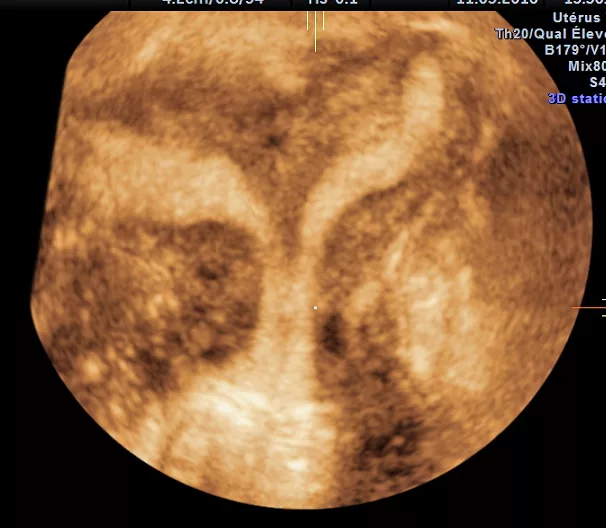

L'Hystérosonographie

Il s’agit d’une échographie pelvienne réalisée par voie endo-vaginale utilisant l’injection de sérum physiologique comme produit de contraste dans la cavité utérine.

- Diagnostic d’une malformation utérine